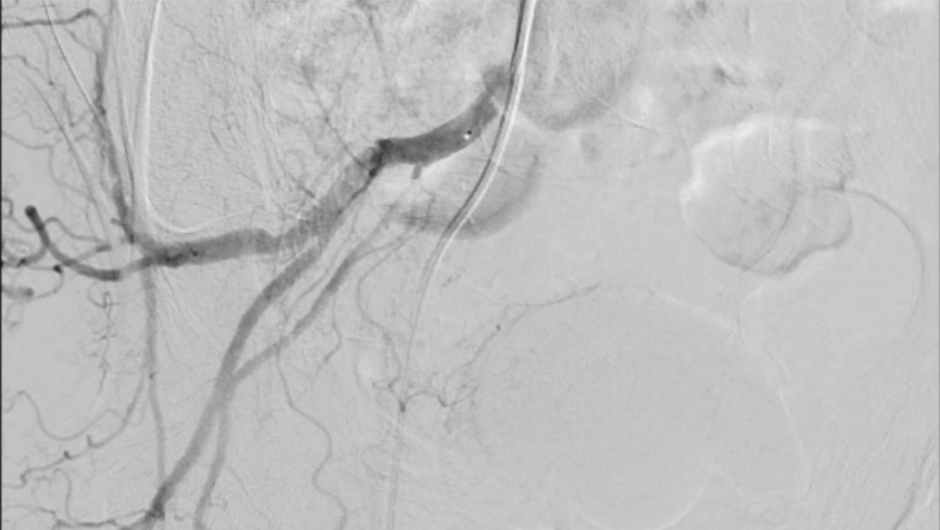

Prostatic Artery Embolization in Benign Prostatic Hyperplasia

Dr. Maurizio Grosso